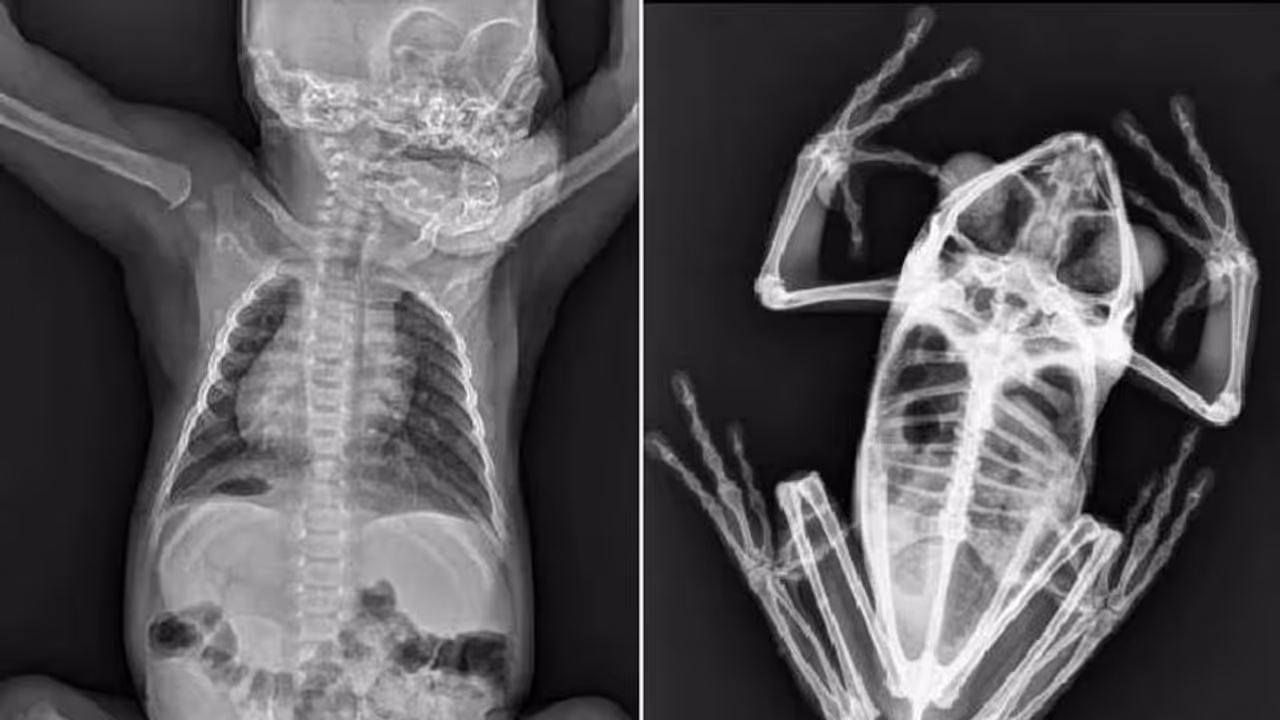

ഒരു നവജാത ഒറാങ്ങുട്ടാന്റെയും ഒരു തവളയുടെയും ആമയുടെയും എക്സ്-റേ ചിത്രങ്ങളാണ് അധികൃതർ സോഷ്യൽ മീഡിയയിലൂടെ പങ്കുവെച്ചത്. ഏറെ അമ്പരപ്പോടെയും കൗതുകത്തോടെയും ആണ് ആളുകൾ ഇതിനെ സ്വീകരിച്ചത്.

മനുഷ്യർ എക്സ്-റേ എടുക്കുന്നത് സർവസാധാരണമാണ്. ശരീരത്തിലെ ആന്തരിക അവയവങ്ങളുടെ അവസ്ഥ എന്താണെന്ന് മനസ്സിലാക്കാൻ പല സാഹചര്യങ്ങളിലും നമ്മൾ എക്സ്-റേ എടുക്കാറുണ്ട്. വളരെ അപൂർവമായി മാത്രമേ മൃഗങ്ങളുടെ എക്സ്-റേ എടുക്കാറുള്ളൂ. കഴിഞ്ഞ ദിവസം സോഷ്യൽ മീഡിയയിൽ ഒരു കൂട്ടം മൃഗങ്ങളുടെ എക്സ്-റേ ചിത്രങ്ങൾ വൈറലായി. സാൻ ഡിയാഗോ മൃഗശാല അധികൃതരാണ് ഈ ചിത്രങ്ങൾ പങ്കിട്ടത്.

സാൻ ഡിയാഗോ മൃഗശാല കഴിഞ്ഞ ദിവസമാണ് ഇൻസ്റ്റാഗ്രാമിൽ വിവിധ ചുറ്റുപാടുകളിൽ താമസിക്കുന്ന മൃഗങ്ങളുടെ എക്സ്-റേ ഫോട്ടോഗ്രാഫുകൾ പോസ്റ്റ് ചെയ്തത്. ഈ ചിത്രങ്ങൾ കണ്ട് സോഷ്യൽ മീഡിയ ഉപയോക്താക്കൾ അമ്പരന്നു എന്നുതന്നെ വേണം പറയാൻ. രണ്ട് ദിവസം മുമ്പ് മൃഗശാലയുടെ ഔദ്യോഗിക ഇൻസ്റ്റാഗ്രാം അക്കൗണ്ടിൽ പോസ്റ്റ് ചെയ്ത ചിത്രങ്ങൾ ഇതിനോടകം തന്നെ ലക്ഷക്കണക്കിന് ആളുകളാണ് കണ്ടത്. പങ്കിട്ട സ്ലൈഡുകളെക്കുറിച്ചും മൃഗശാല അധികൃതർ വിശദീകരിച്ചു. ഷെയർ ചെയ്തതിന് ശേഷം, പോസ്റ്റ് 29,000 -ലധികം ലൈക്കുകളും നിരവധി കമന്റുകളും നേടി.